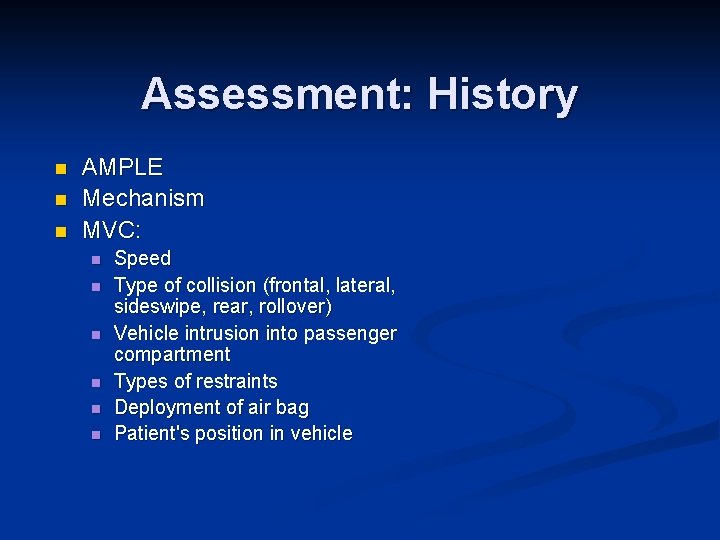

Assessment: History n n n AMPLE Mechanism MVC: n n n Speed Type of collision (frontal, lateral, sideswipe, rear, rollover) Vehicle intrusion into passenger compartment Types of restraints Deployment of air bag Patient's position in vehicle